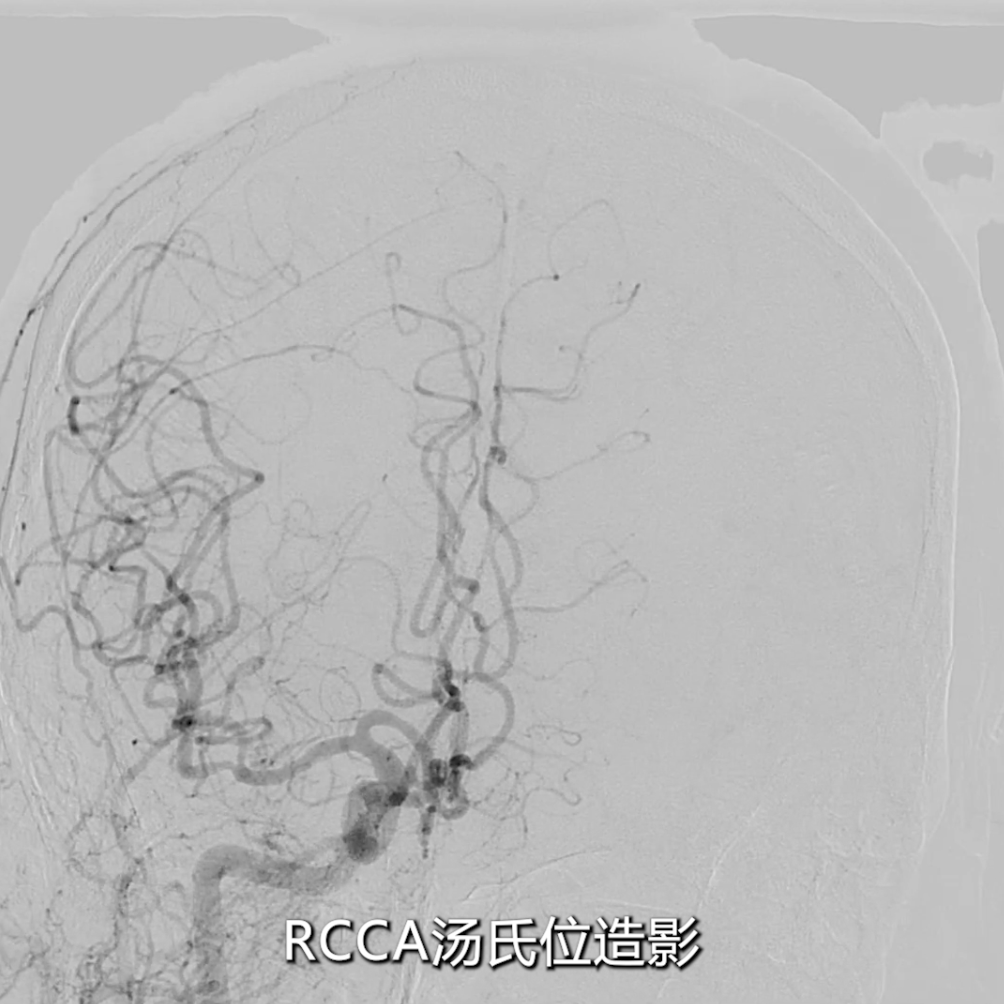

★ 病变评估

右侧颈总动脉造影(正位、汤氏位、侧位):明确右侧颈内动脉重度狭窄,病变远端直径5mm、近端直径8mm,长度约30mm,远端锚定区条件理想。